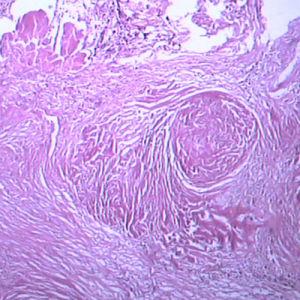

游離二氧化矽含有游離二氧化矽的粉塵進入人的肺內後,在二氧化矽的毒作用下,引起肺巨噬細胞解壞死、導致肺組織纖維化,形成膠

原纖維結節,使肺組織彈性喪失,硬度增大,造成通氣障礙,影響肺的呼吸活動,即人吸入游離二氧化矽的粉塵可引起

二氧化矽的量越高,對人體危害越大,甚至有可能導致癌症的發生。矽肺。矽肺是塵肺中進展最快、危害最重的一種。粉塵中含有游離